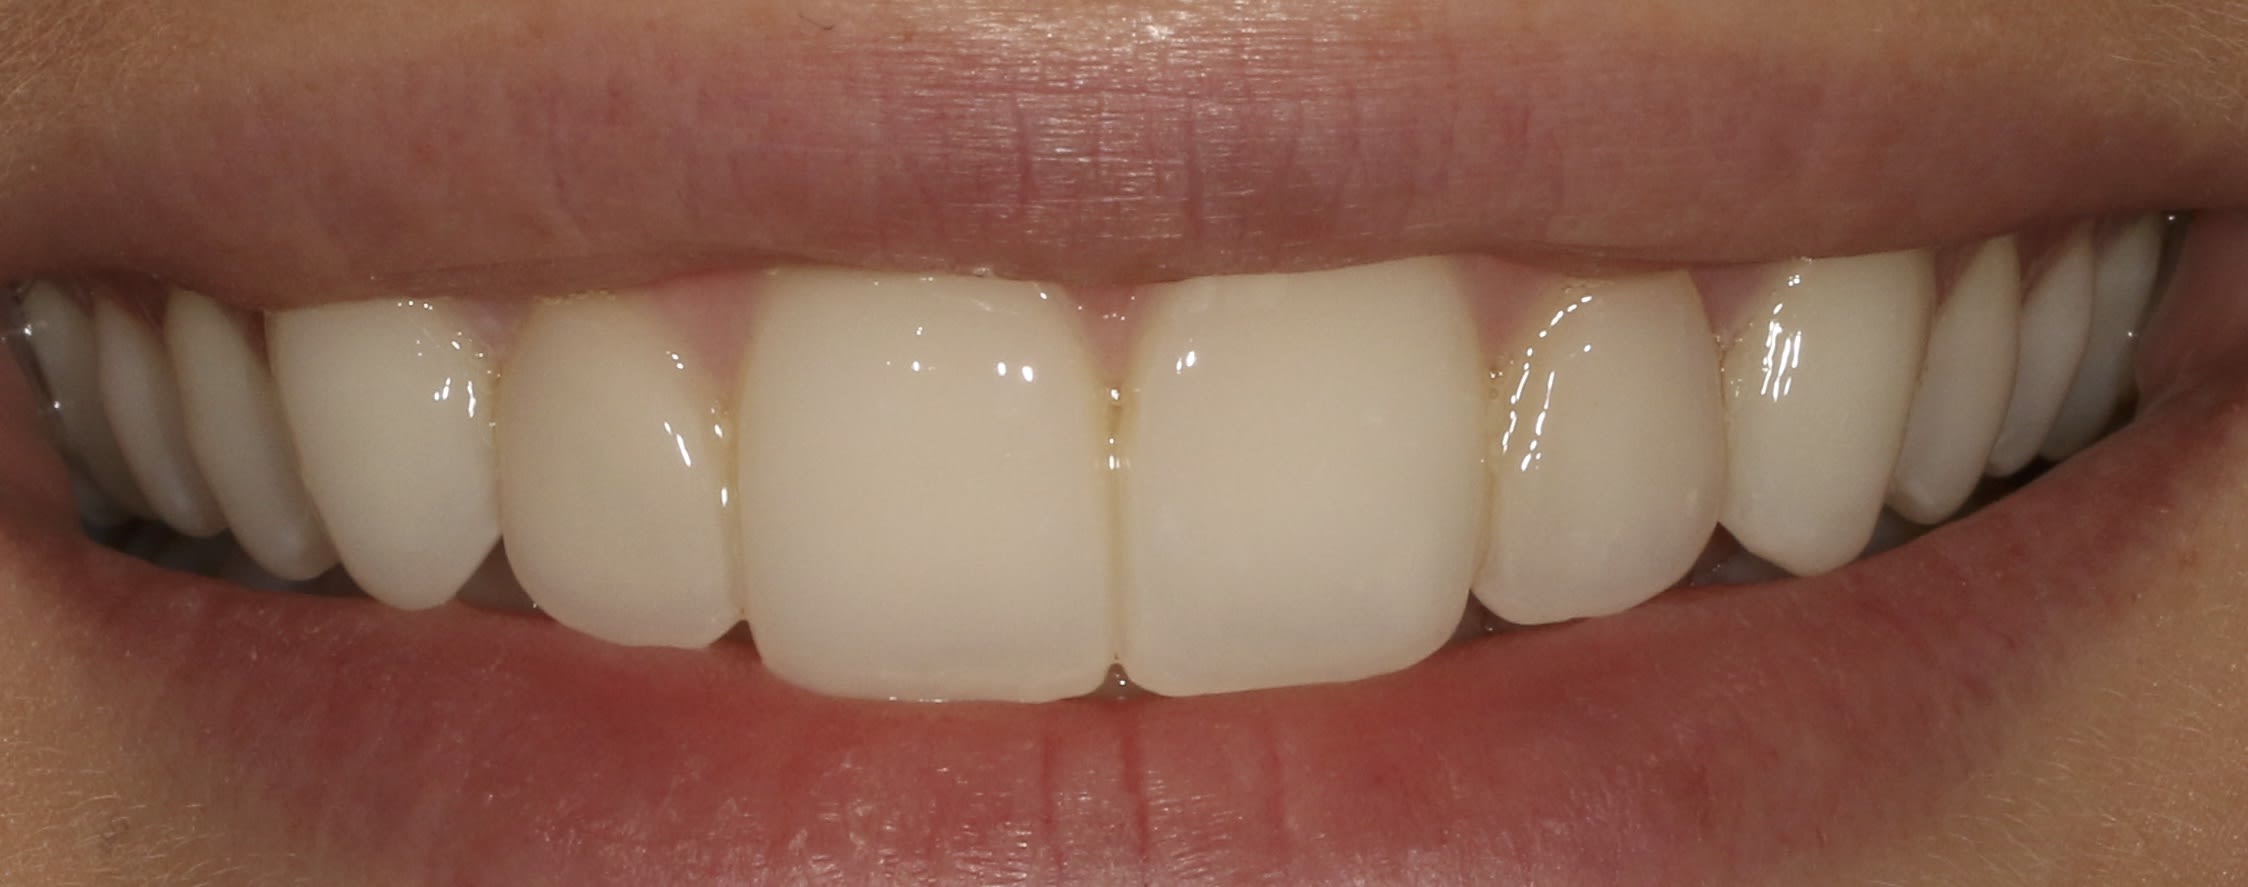

Un p'tit dernier pour la route, avec un visuel à 6 mois

C'est vrai que ça se salit à donf c'te saloperie, bon c'est vrai aussi qu'un p'tit polissage de 15 minutes suffit à leur redonner de l'éclat.....mais chut faut pas le dire, faudrait pas frustrer le gamin.

Tout cela est parfaitement splendide.

Comme j'aime ergoter, je te dirais que des cerams auraient eu une meilleure influence sur la paro du dernier, et auraient peut-être mis moins de temps à réaliser finalement, mais cela n'enlève rien à la maîtrise technique.

74 ans, une abrasion à plus de 50% sur les inf. et une putain de classe 2 compensée par une sale tendance à la propulsion pour bien niquer les faces palatines des sups et exploser les infs.

Primo en Céram j’y vais pas, comme dit Enlaye: je me cague de le faire.....,et c’est vraiment